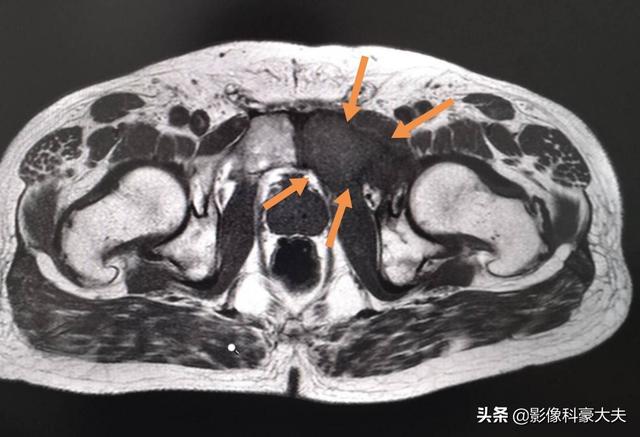

Dieser Patient.Schmerzen in der linken Hüfte, Befürchtung einer Hüftkopfnekrose, entpuppte sich als Knochenmetastase bei Lungenkrebs.

Der Ort der Knochenmetastasierung hängt in der Regel mit der primären Krebsläsion zusammen, und im Allgemeinen ist die Wahrscheinlichkeit einer Metastasierung umso größer, je näher der Abstand zum Tumor ist. Bei Brustkrebs finden sich aufgrund der Lage im Brustkorb am häufigsten Brustbein- und Rippenknochenmetastasen, gefolgt von den Brust- und Lendenwirbeln der Wirbelsäule; bei Knochenmetastasen von Lungenkrebs sind die Wirbelsäule und die Gliedmaßen die häufigsten Lokalisationen; bei Nieren- und Gebärmutterhalskrebsmetastasen sind Lendenwirbel- und Beckenmetastasen am häufigsten; und bei Prostatakrebsmetastasen sind die gesamte Wirbelsäule und die Gliedmaßen betroffen.